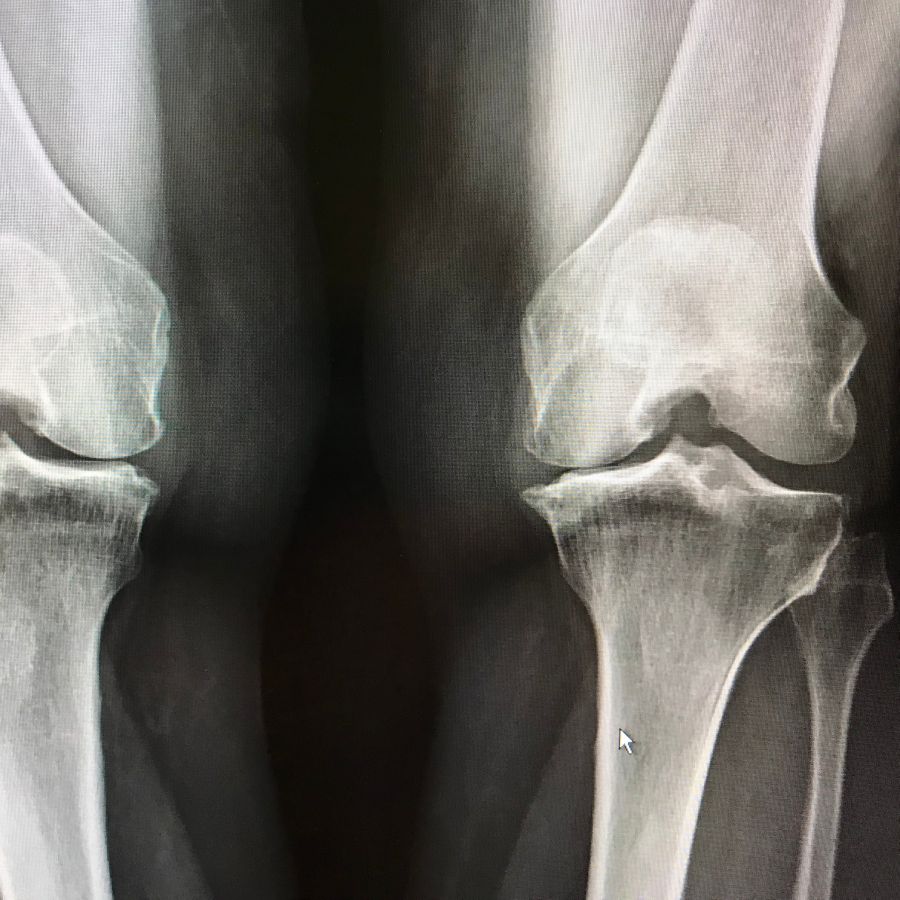

Rodilla